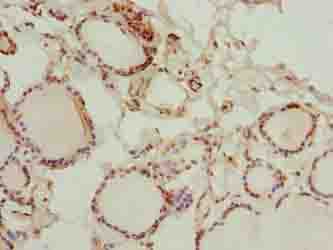

Backgroundcytoplasm

ApplicationELISA, IHC; Recommended dilution: IHC:1:20-1:200